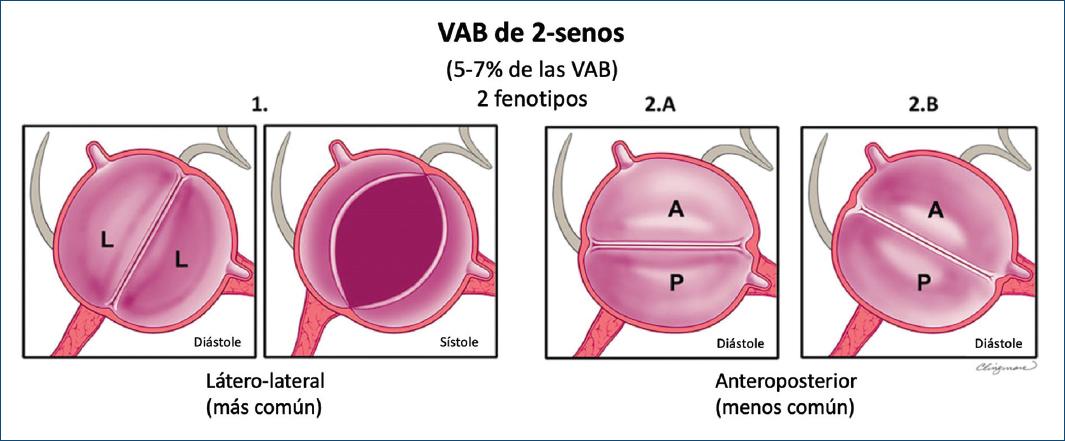

VÁLVULA AÓRTICA BICÚSPIDE DE DOS SENOS

La VAB de tipo dos senos es poco común, representando aproximadamente el 5-7% de los casos de VAB2,6,28. En contraste con el tipo fusionado, la apariencia de la VAB de dos senos no sugiere que dos de las tres cúspides se hayan fusionado, sino que hay dos cúspides de aproximadamente el mismo tamaño y forma, que cada una ocupa 180° de la circunferencia anular, y que estas se «formaron» dentro de dos senos aórticos solamente, lo que resultó en una válvula de dos senos/dos cúspides (Figs. 11 y 12) con ángulos comisurales de 180°. Es difícil determinar cuáles dos cúspides podrían haberse unido para formar una VAB de dos senos, pero generalmente es evidente si las cúspides son latero-laterales (de lado a lado) o antero-posteriores (adelante y atrás) dentro del plano de la base del corazón de eje corto (Figs. 11 y 12); por lo tanto, estos son los dos fenotipos específicos de la categoría de la VAB de dos senos. La VAB latero-lateral de dos senos tiene una arteria coronaria que surge de cada seno, mientras que la VAB antero-posterior puede tener una arteria coronaria que surge de cada seno o ambas arterias coronarias que surgen del seno anterior (Figs. 11 y 12). La VAB de dos senos probablemente representa una expresión más grave de los mecanismos embriológicos que conducen a la VAB fusionada. Es apropiado referirse a estos fenotipos como VAB latero-lateral de dos senos y VAB antero-posterior de dos senos. Ocasionalmente, a pesar de la sospecha, puede ser difícil estar seguro de si solo hay dos senos, en cuyo caso se pueden usar términos como posible o probable VAB de dos senos. Hay una falta de datos científicos sobre las asociaciones clínicas/pronósticas de la VAB de dos senos, que representa una forma «morfológicamente severa» de la VAB. Por lo tanto, esperamos que por medio de este sistema de nomenclatura/clasificación, la comunidad investigadora dirija más atención hacia este tipo de VAB.

Figura 11 Esquema de los fenotipos de la válvula aórtica bicúspide (VAB) de tipo dos senos vistos por el ecocardiograma transtorácico en eje corto paraesternal. Aplicable a vistas tomográficas similares obtenidas de la tomografía computarizada cardiaca y resonancia magnética cardiaca, la figura muestra fenotipos de VAB de dos senos como vistas ampliadas de la base del corazón para la correlación anatómica con los puntos de referencia. 1: VAB de tipo dos senos latero-lateral con solo dos senos aórticos distinguibles en diástole y dos cúspides de aproximadamente el mismo tamaño y forma, cada una ocupando 180° de la circunferencia, con un ángulo de 180° de las comisuras. Nótese que aunque es posible sospechar fusión derecha-no coronaria, las referencias anatómicas no están claras porque tanto las cúspides «izquierda» como «no coronaria» ocupan porciones de la ubicación anatómica normal de la cúspide «no coronaria», y la línea comisural posterior está casi alineada con el septum interauricular, dividiendo la ubicación anatómica de la cúspide no coronariana normal (Figs. 5 y 12). La VAB de tipo dos senos fenotipo latero-lateral tiene una arteria coronaria que surge de cada seno. 2A: una VAB de tipo dos senos fenotipo antero-posterior con solo dos senos aórticos distinguibles en diástole y dos cúspides de aproximadamente el mismo tamaño y forma, cada uno ocupando 180° de la circunferencia, con un ángulo de 180° de las comisuras. Nótese que aunque es posible sospechar fusión derecha-izquierda, las referencias anatómicas no están claras porque la línea comisural en realidad divide la ubicación anatómica normal de la cúspide izquierda, de modo que tanto la cúspide funcional anterior como la posterior parecen tener una «parte» de la cúspide izquierda normal (Figs. 5 y 12). 2B: una VAB de tipo dos senos fenotipo antero-posterior que se asemeja a una fusión derecha-izquierda fusionada pero sin rafé, con solo dos senos aórticos distinguibles en diástole y dos cúspides del mismo tamaño/forma, cada uno ocupando 180° de la circunferencia. La VAB antero-posterior de dos senos puede tener arterias coronarias que surgen de cada cúspide (2A) o desde la cúspide funcional anterior (2B) (modificada de Michelena et al., 20206 con permiso de Elsevier).